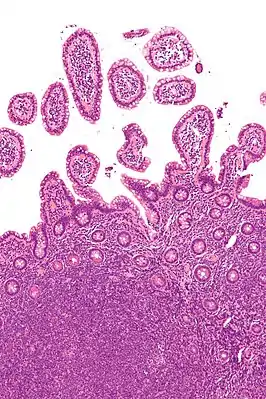

![]() Микрофотография, показывающая мантийноклеточную лимфому (внизу изображения) в биоптате терминального отдела илеуса. Окраска гематоксилин-эозином. | |